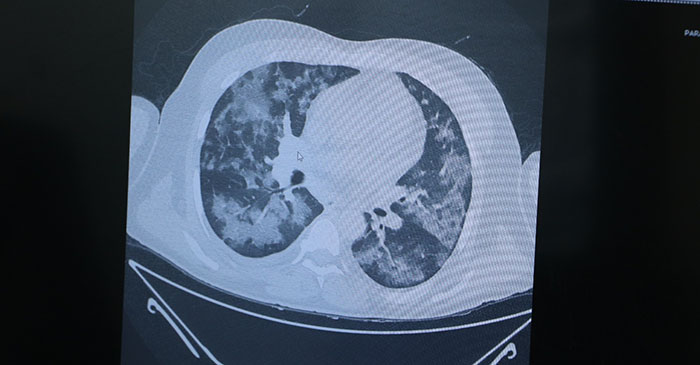

Özellikle Karadeniz Bölgesi’nde vakaların artış nedenini sorgulamaya başladıklarını ifade eden Özkaya, “Gerçekten çok kötü hastalar gelmeye başladı. Karadeniz Bölgesi’nin yaşam stili böyle olabilir. Karadenizlilerde genelde hala oğlu, amca oğlu, dayı oğlu diye geçerler. Çünkü hep beraber bir arada yaşarlar. Ya aynı apartmanda ya da aynı köyde yan yana yaşarlar. Karadeniz insanı tez canlıdır, heyecanlıdır, çok hızlı düşünür, hızlı karar verir ve çok fevri davranır. Düğünlerini, cenazelerini, üzüntülerini, sevinçlerini hep beraber yaşamak isterler. Çok fazla hastalanacağım korkusu yaşamadan her türlü yardıma koşarlar. Bunun getirdiği olumsuzluklar da var, yani toplu halde bir arada yaşamanın dışında biz acaba bu yeni mutasyonun Karadeniz’de çok hızlı etkilediğini mi düşünüyoruz. Çünkü ailede bir kişi enfekte olunca bütün aileyi enfekte ediyor. Yani bu önceden beklediğimiz bir durum değildi. Önceden ailede 1-2 kişi enfekte olurdu, diğerlerini izolasyonla korurduk ama şimdi öyle değil. Bir kişi enfekte olunca bütün aile hızla enfekte oluyor. Bunu ancak mutasyonla açıklayabileceğimizi düşünüyoruz. Çünkü gerçekten virüs kendini değiştiriyor ve geliştiriyor. Biz kişilere mümkün olduğunca bir arada olmayın diyoruz ama mutasyonla da baş etmemiz lazım” diye konuştu.